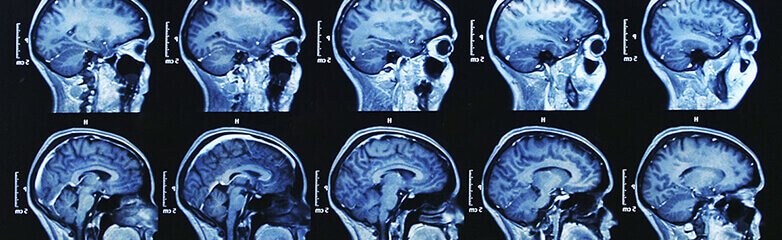

The Department of Radiology at P.P. Maniya Hospital is one of the finest centres of its kind. New high performance equipment together with a hospital-wide, all digital imaging, archival and retrieval system establishes P.P. Maniya Hospital as an important referral site. This state-of-the-art technology facilitates rapid communication and diagnosis.

- Magnetic Resonance Imaging (3T MRI)

- Our 3 Tesla MRI scanner is among the most advanced equipment in India. Capabilities include basic and advanced imaging in Neuro, Body imaging and Musculo-skeletal imaging.